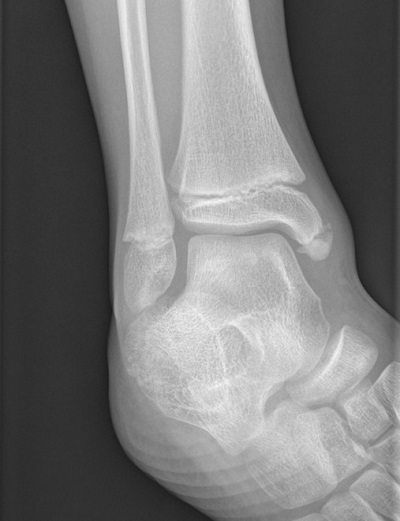

Niño de 12 años derivado desde la consulta de Atención Primaria por sospecha de fractura de maleolo tibia. Se realizó una radiografía de tobillo (Figura 1) por dolor en el maleolo externo de 3-4 días de evolución tras sufrir una eversión forzada.

Figura 1. Os subtibiale, hueso supernumerario

Tras una exploración completa y revisión de radiografías de tobillo previas donde ya se objetivaba la lesión, se diagnostica de os subtibiale.

El os subtibiale es un hueso accesorio muy poco frecuente, por lo general de diagnóstico incidental, de 4 a 15 mm de tamaño, con una prevalencia estimada del 0,7 al 1,2%. Se localiza distal o posterior al maléolo medial, de morfología redondeada y cortical bien definida. Generalmente no tiene implicación clínica, pero en algunos casos puede producir dolor y limitación de la movilidad en el tobillo, aunque existen muy pocos casos reportados.

El diagnóstico se realiza mediante radiografía convencional con proyecciones anteroposterior y lateral de ambos tobillos, pues en muchas ocasiones es bilateral.

La presencia de os subtibiale se puede interpretar como una fractura, especialmente si existen antecedentes de traumatismo, como en nuestro caso clínico. Un error en el diagnóstico puede llevar a una innecesaria inmovilización o, en casos con mala evolución, a cirugía.